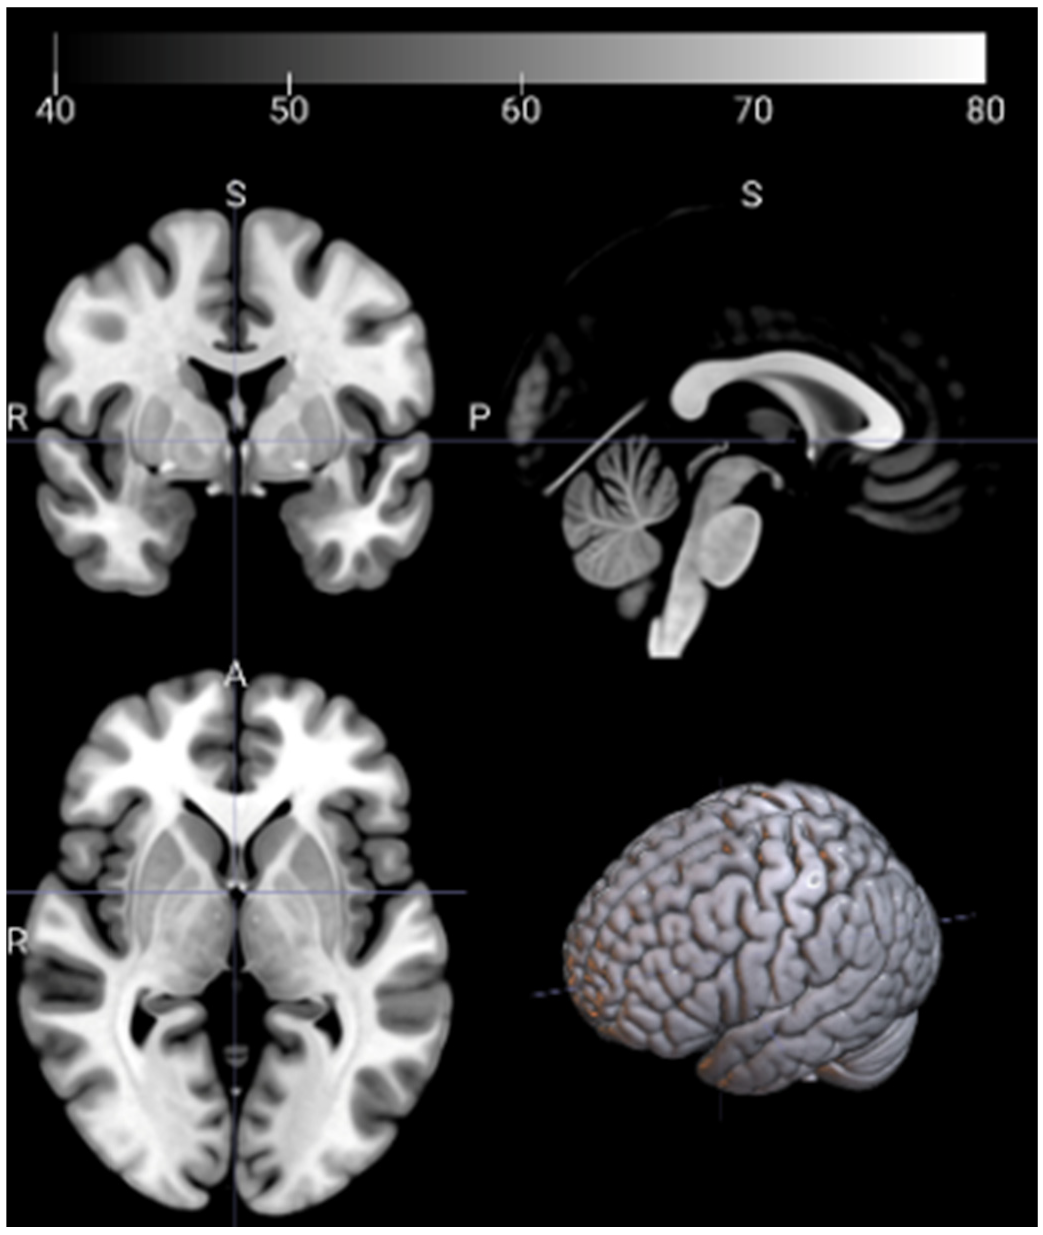

2.3. Image Preprocessing and Feature Extraction